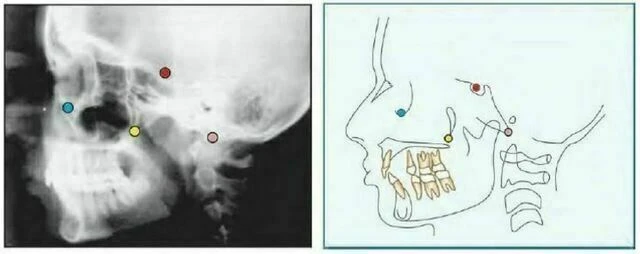

Orbitale (Or) là điểm nằm ở vị trí thấp nhất trên xương ổ mắt. Trên phim cephalogram theo chiều trước sau, mỗi điểm nằm riêng biệt nhau nhưng trên phim cephalogram mặt bên thì đường viền xương ổ mắt trùng nhau. Thông thường, điểm thấp nhất trên đường trung bình của xương ổ mắt được dùng để xác định mặt phẳng Frankfort.

Gonion (Go) là điểm nằm ở vị trí sau nhất và thấp nhất ở góc xương hàm dưới. Nó có thể được xác định bằng cách xem xét thông thường hoặc bằng cách chia đôi góc tạo bởi đường giao nhau của cành đứng và cành ngang xương hàm dưới, cho đường phân giác góc này cắt đường viền xương hàm dưới.

Pterygomaxillary Fissure (Ptm) Có một hình ảnh có hình giọt nước, bóng phía trước là mặt sau của lồi cùng xương hàm trên. Điểm Ptm là giao của biên giới phía dưới của lỗ tròn với thành sau của khe chân bướm hàm.